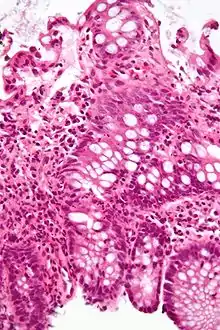

Micrograph showing intestinal crypt branching, a histopathological finding of chronic colitis. H&E stain.

An important investigation in the assessment of colitis is biopsy for histopathology. A very small piece of tissue (usually about 2mm) is removed from the bowel mucosa during endoscopy and examined under the microscope by a histopathologist. A biopsy report generally does not state the diagnosis, but should state any presence of chronic colitis, give an indication of disease activity, as well as state the presence of any epithelial damage (erosions and ulcerations).[4]

Histopathology findings generally associated with chronic colitis include:[4]

Other findings include basal plasmacytosis and mucin depletion.[4] Histopathology findings generally associated with active colitis include:[4]